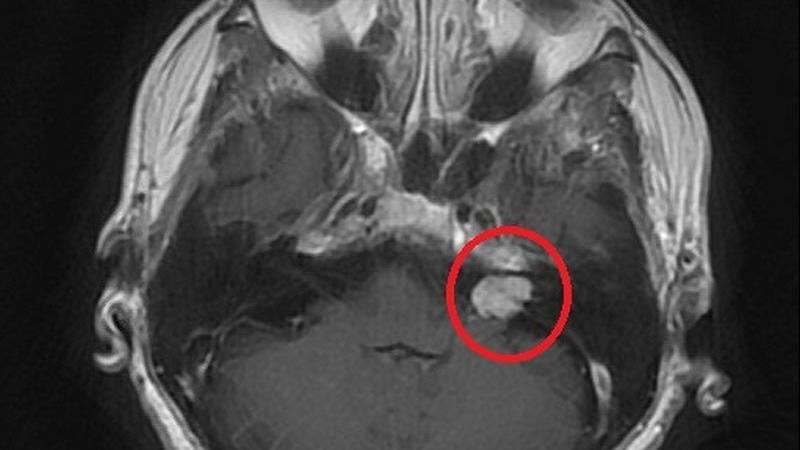

▲術前核磁共振顯示紅圈處有一小於2公分大的腫瘤。(圖/台北慈濟醫院提供)

徐賢達主任說明:「聽神經瘤屬於常見良性腦瘤,根據不同地區和研究,聽神經瘤的盛行率大約在十萬分之一到二左右,多數發生在單側,且生長速度很慢,容易被誤以為是聽力退化。」但當腫瘤生長大於2公分且壓迫到聽神經或顏面神經時,就可能會有聽力損失、耳鳴、耳朵有壓力感等症狀,嚴重可能導致平衡異常、面部麻木。若是沒有及時處置,使腫瘤進一步成長壓迫至腦幹,就會有危及生命的風險。